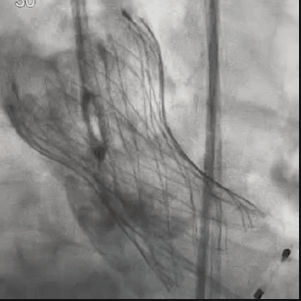

为期两天的手术联播过程中,来自厦门大学心血管病医院王斌教授,首都医科大学附属北京安贞医院宋光远教授,阜外华中心血管病医院王圣教授,南京医科大学第一附属医院孙伟教授,广东省人民医院李捷教授,中国医学科学院阜外医院吴永健教授,中南大学湘雅二医院方臻飞教授,浙江大学医学院附属第二医院王建安教授,北京大学第三医院唐熠达教授分别带来了精彩的TAVR实战案例。

从三叶瓣重度钙化到二叶瓣畸形的根部解剖,从单纯主动脉瓣反流到入路极端迂曲挑战的案例。TaurusOne凭借其优异的柔顺性,支撑力强及内外层双侧裙边的特点,都能从容应对复杂的临床患者解剖结构。从患者的临床选择到术后的长久获益,从手术入路的种类到术中操作的注意事项,从围术期卒中的循证医学到术后的抗凝抗栓用药规范,在线专家共同交流彼此中心的围术期TAVR经验和分享现阶段经导管主动脉瓣置换的诊疗策略。针对当前TAVR领域多个热点学术问题进行了热烈的讨论,现场可谓精彩纷呈、高潮迭起。专家们纷纷借此契机相互交流探讨,分享各自的单中心经验,力求进一步提升TAVR手术的安全性和有效性,为主动脉瓣相关疾病的患者带来长远综合获益。